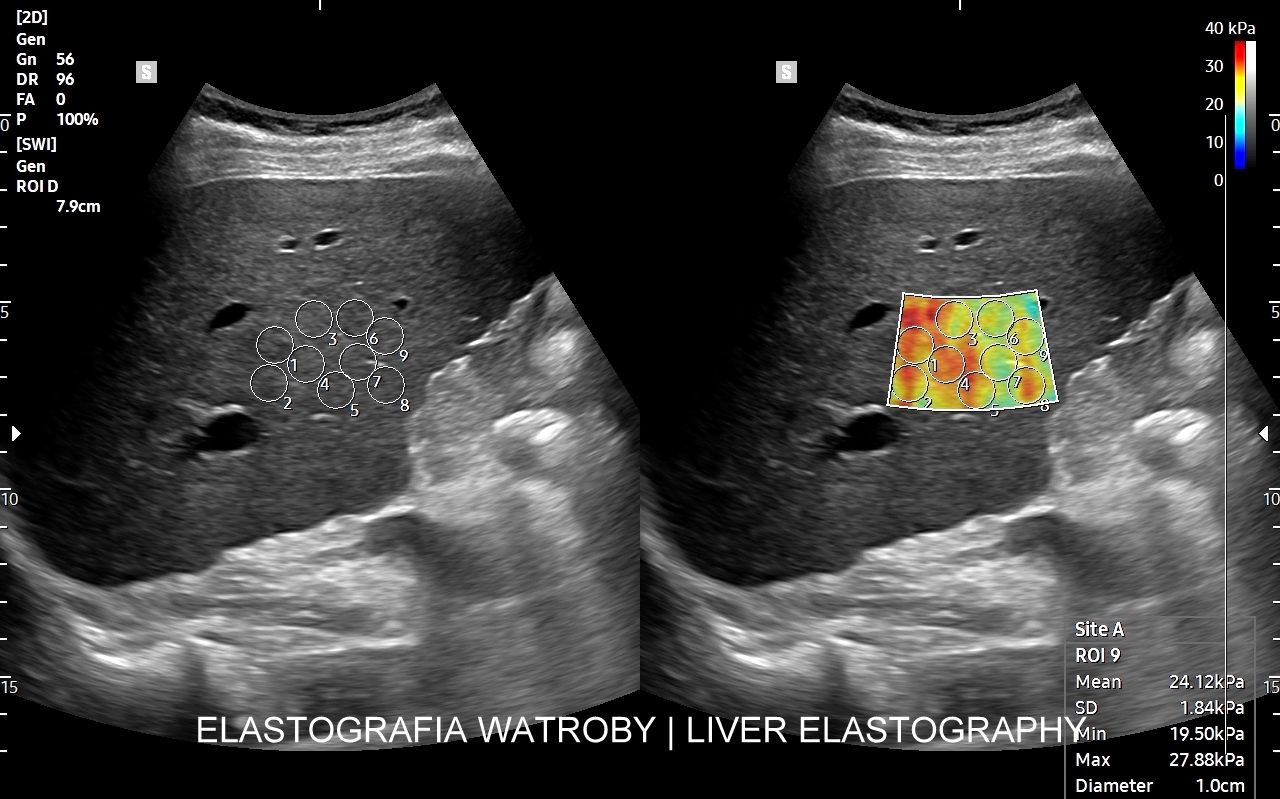

Na przestrzeni czasu metoda SWI ulegała ewolucji. Jej starsza odmiana to tzw. Fibroscan, który jest badaniem „na ślepo”, gdyż nie umożliwia precyzyjnego wyboru miejsca oceny miąższu wątroby. Odmianą najnowszą i wysoce precyzyjną jest elastografia 2D-SWE (2D sheer wave elastography). W badaniu 2D-SWE możliwy jest wybór konkretnego miejsca pomiaru w obrębie wątroby; dodatkowo generowana jest mapa kodowaną kolorem odpowiadająca mnogim punktom pomiaru, które następnie w trakcie post-processingu można wybrać w celu uzyskania dokładnego i wiarygodnego wyniku.

W jakim celu wykonywana jest elastografia wątroby? Elastografia 2D-SWE precyzyjnie ocenia sztywność miąższu wątroby, która to wzrasta w procesie włóknienia na tle przewlekłych schorzeń narządu, np. zapaleń. Badanie pozwala w ten sposób ocenić stopień zaawansowania zwłóknienia lub marskości wątroby. Dokładność oszacowania zwłóknienia w elastografii 2D-swe jest na tyle precyzyjna, iż zastępuje ona w omawianym wskazaniu medycznym biopsję wątroby.